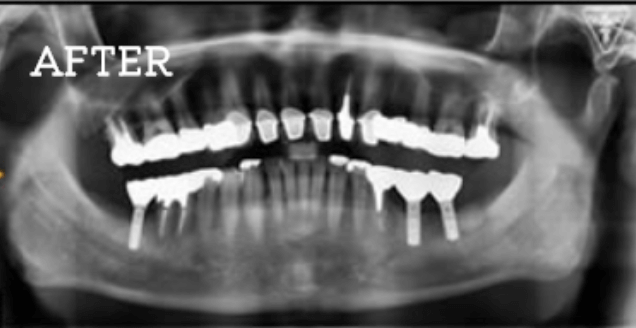

症例

お困りごとを参考に、治療のbefore・afterが確認できます。治療過程や期間、費用などを参考にご覧ください。